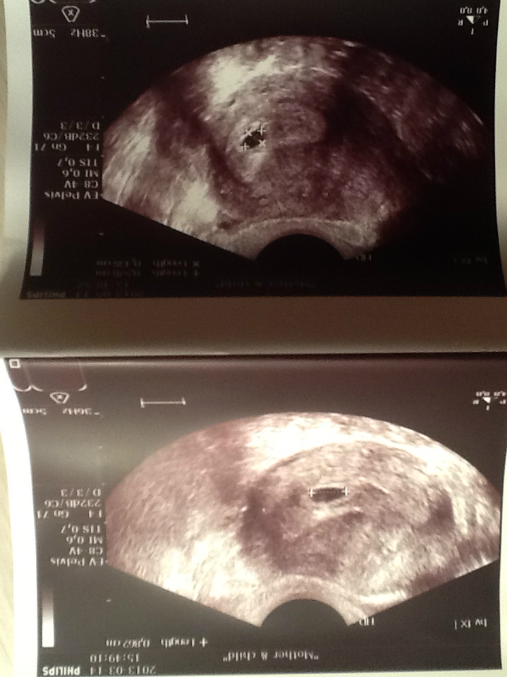

вот собственно говоря с чего началось наше ожидание чудо...и первое фото малыша на 5-6 недельке... Увидев две плоски на тесте(хотя вторая была изначально еле видна)...я просто ошалела от радости! долго ждали и надеялись:) рости наша кроха:)